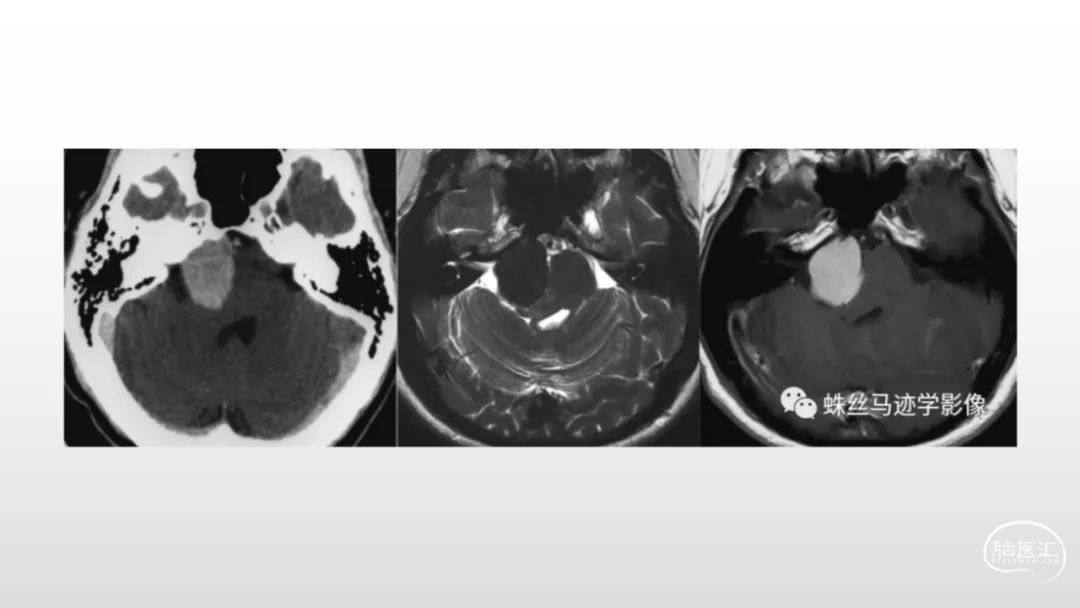

颅脑影像诊断基础知识讲座:脑膜病变

马洪舟

菏泽市立医院